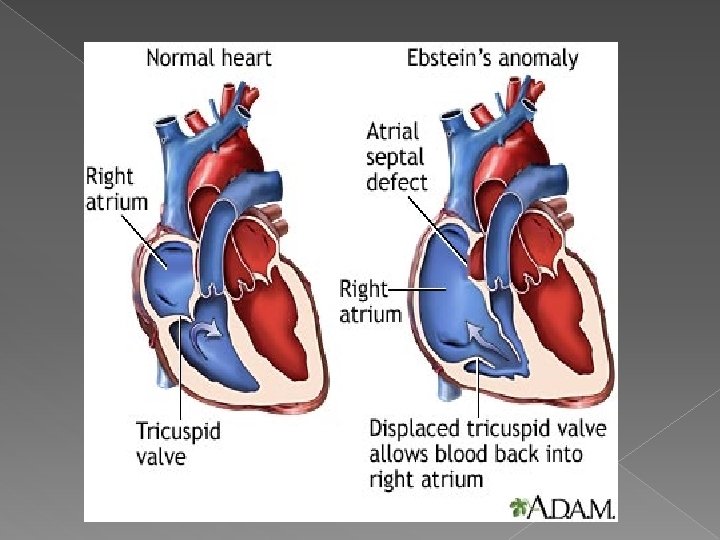

Ebstein's anomaly is a congenital heart defect in which the opening of the tricuspid valve is displaced towards the apex of the right ventricle of the heart. � This causes the right atrium to be large and the anatomic right ventricle to be small in size. � There may be an increased risk of this abnormality in infants of women taking lithium during the first trimester of pregnancy � While Ebstein's anomaly is defined as the congenital displacement of the tricuspid valve towards the apex of the right ventricle, it is often associated with other abnormalities �